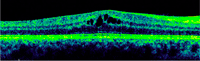

3-5. Tanto el EMQ como el EMD pueden asociarse a DRS (

Tabla 2 y

Figura 4,

Figura 5,

Figura 6 y

Figura 7).

Tabla 2. Características de OCT de los 3 subtipos de edema macular.

Figura 4. Edema macular quístico (EMQ).

Figura 5. Edema macular difuso (EMD).

Figura 6. Desprendimiento de retina seroso (DRS) en una paciente con uveítis asociada a enfermedad de Behçet.

Figura 7. Desprendimiento de retina seroso subfoveal asociado a edema macular quístico en una paciente con coroidopatía tipo Birdshot.